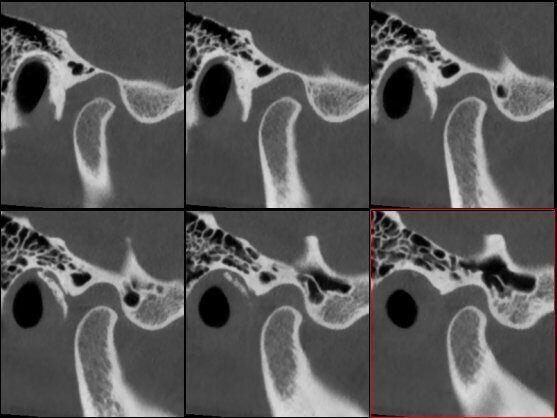

ATM Bocca Aperta